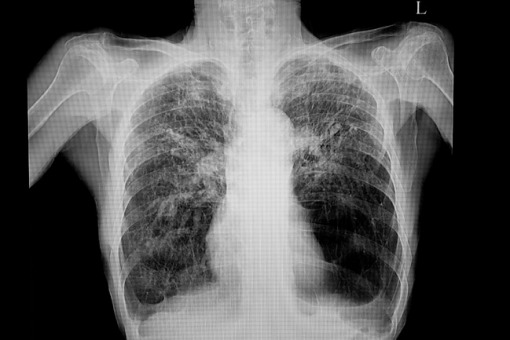

Rozedma sprzyja rozwojowi raka płuc

Im bardziej nasilona rozedma płuc, tym wyższe ryzyko raka tego narządu – informuje pismo „Radiology”.

Rozedma to przewlekła choroba układu oddechowego charakteryzująca się uszkodzeniem pęcherzyków płucnych. Jej objawy to duszność, kaszel ze śluzem, świszczący oddech i ucisk w klatce piersiowej. Choć nie ma leczenia przyczynowego, dostępnych jest wiele terapii pomagających w radzeniu sobie z objawami.

Naukowcy przeanalizowali wyniki badań z trzech dużych baz danych dotyczące związku pomiędzy rozedmą płuc a rakiem płuc. Analiza 21 badań z udziałem ponad 107 000 pacjentów wykazała związek pomiędzy ocenianym metodą tomografii komputerowej nasileniem rozedmy a ryzykiem raka płuc.

– Nasza metaanaliza wykazała, że nie tylko oceniana wizualnie, ale także oceniana ilościowo rozedma płuc w tomografii komputerowej jest związana z rakiem płuc, i że ryzyko to wzrasta w przypadku bardziej nasilonej rozedmy – powiedziała dr Vonder.